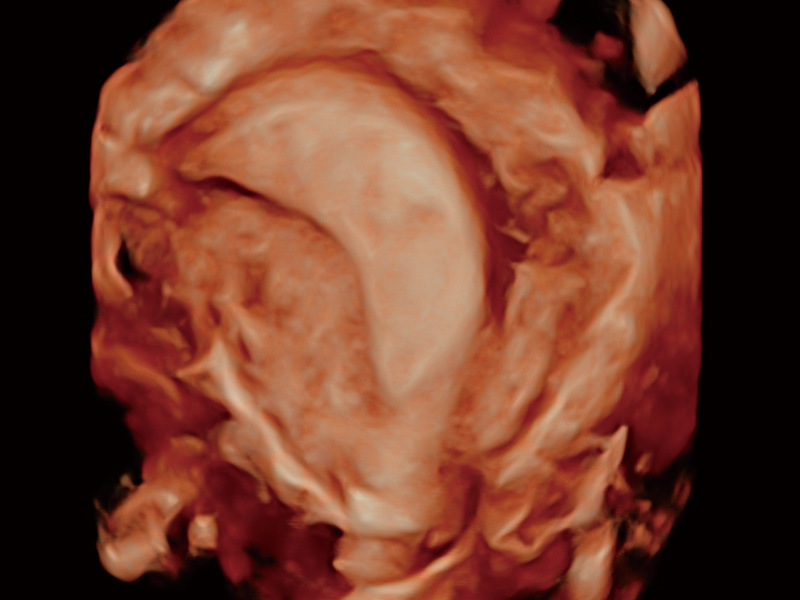

腔内容积探头

腔内三维成像技术获得显著提升,超大扇角在满足日常基础扫查的同时,支持卵泡自动测量及多种三维渲染模式,为您提供更多的诊断信息,尤其是在子宫畸形的诊断,内膜及肿瘤占位观测中起到了重要的作用。

超声引导下胚胎移植

单角子宫

子宫内膜息肉